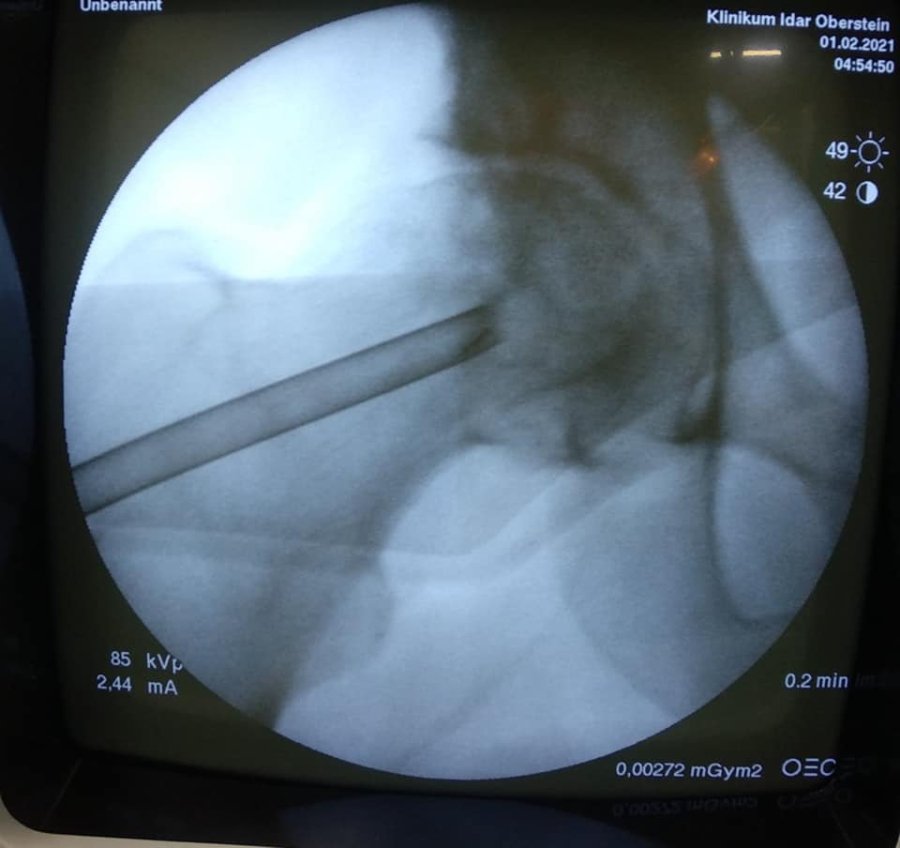

Ця операція полягає у видаленні вмісту кисти, очищенні її стінок та виповнення дефекту кістковим трансплантатом з доступу розміром 3 см.